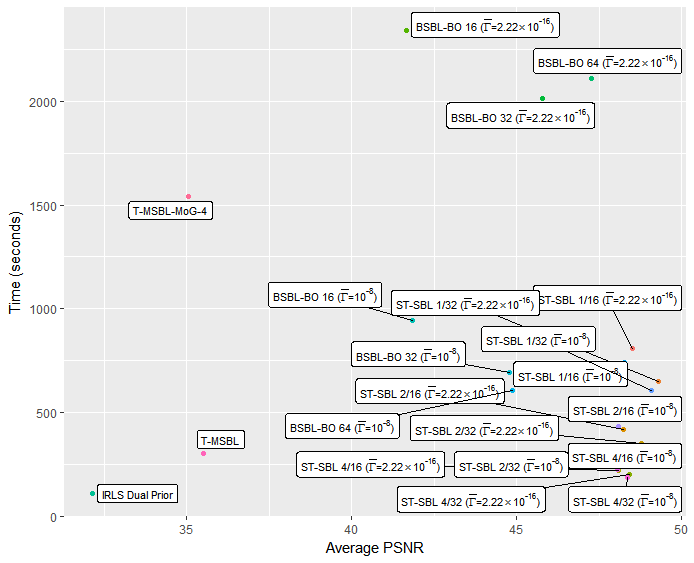

Whilst we are primarily concerned with the quality of the reconstruction, the time taken for various reconstruction methods is of some practical interest. Figures 5 and 6 show plots of average time against the average PSNR achieved. For these timings, the algorithms were run using MATLAB 2014a on computer equipped with an i7-3770 processor and 8GB of RAM. Although processing more than a single column at a time with ST-SBL does not typically lead to improved recovery performance, the drop in performance is minimal, and as seen in figures 5 and 6, there is a significant reduction in computational time required by processing multiple columns at once.

Overall, the best recovery performance was achieved with ST-SBL 1/32 () . However, once we take the computational time into account, we would consider ST-SBL 4/32 () to be the best practical choice, as it offers only a minimal decrease in performance, and a very significant reduction in the computational time required.